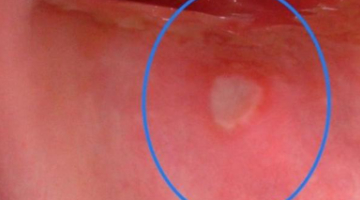

Practice

Here is a practice image in Figure 2. Try to describe it using the eight components of good oral lesion descriptions. For this example, take a guess the consistency and texture. (This is only for practice!)

Go through each item on your list:

- Location

- Distribution and definition

- Size

- Shape

- Color

- Consistency

- Texture

You can find how I charted this lesion on this page. Practice your skills and soon you will be a pro at detecting and charting oral lesions!